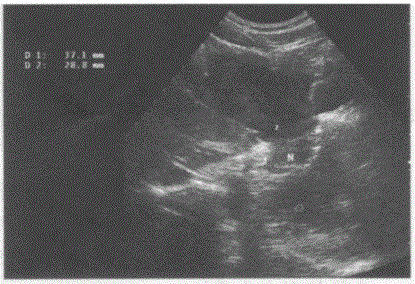

问题 临床资料:女,34岁,自述进食后上腹部不适。 超声综合描述:腹主动脉下腔静脉前方可见10.1cm×9.3cm形态不规则低回声,边界清晰,内回声不均匀,肝左叶受其推挤形态失常。 超声提示:

选项 A.胰腺癌 B.胃平滑肌肉瘤 C.肝癌 D.腹腔肿大淋巴结

答案 B